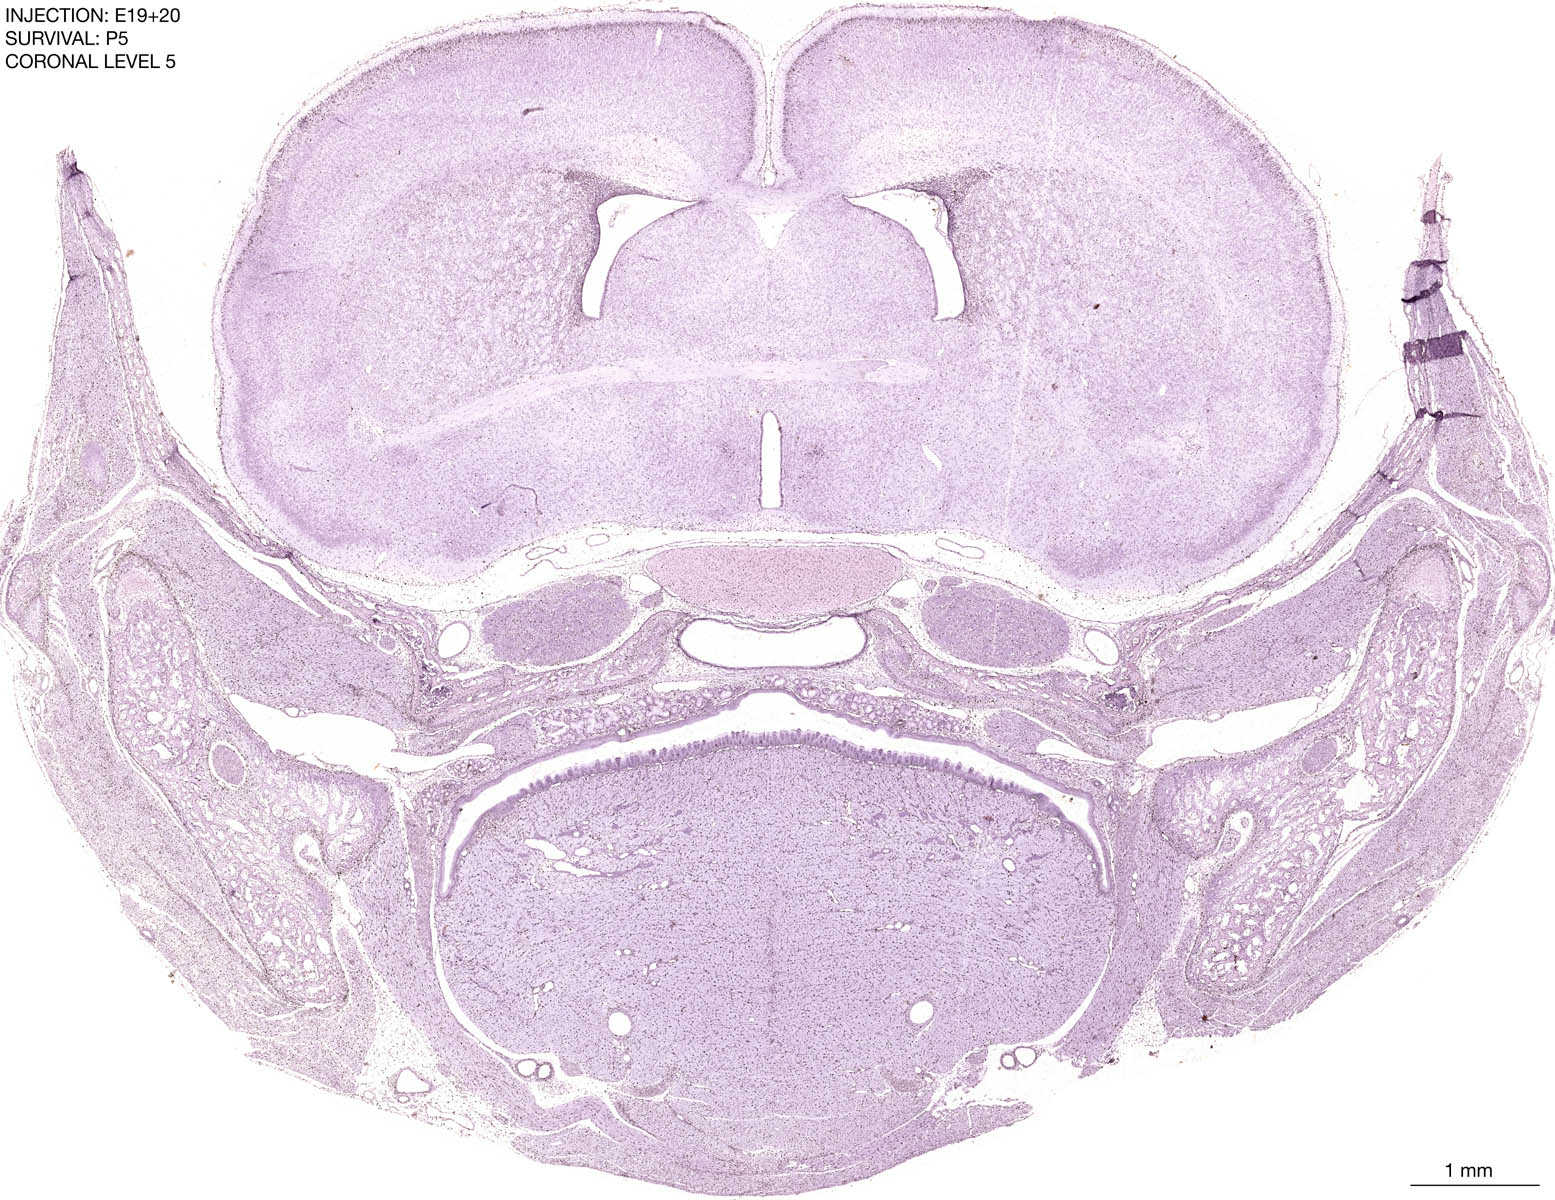

E19+20 P5 Survival The images below are from the brain of a rat that was exposed to tritiated thymidine on E19+20 and survived to P5. Download: Large | High Res Download: Large | High Res Download: Large | High Res Download: Large | High Res Download: Large | High Res Download: Large | High Res Download: Large | High Res Download: Large | High Res Download: Large | High Res Download: Large | High Res Download: Large | High Res Download: Large | High Res Download: Large | High Res Download: Large | High Res Download: Large | High Res Download: Large | High Res Download: Large | High Res Download: Large | High Res Download: Large | High Res Download: Large | High Res Download: Large | High Res Download: Large | High Res Download: Large | High Res Download: Large | High Res Download: Large | High Res Download: Large | High Res Download: Large | High Res Download: Large | High Res